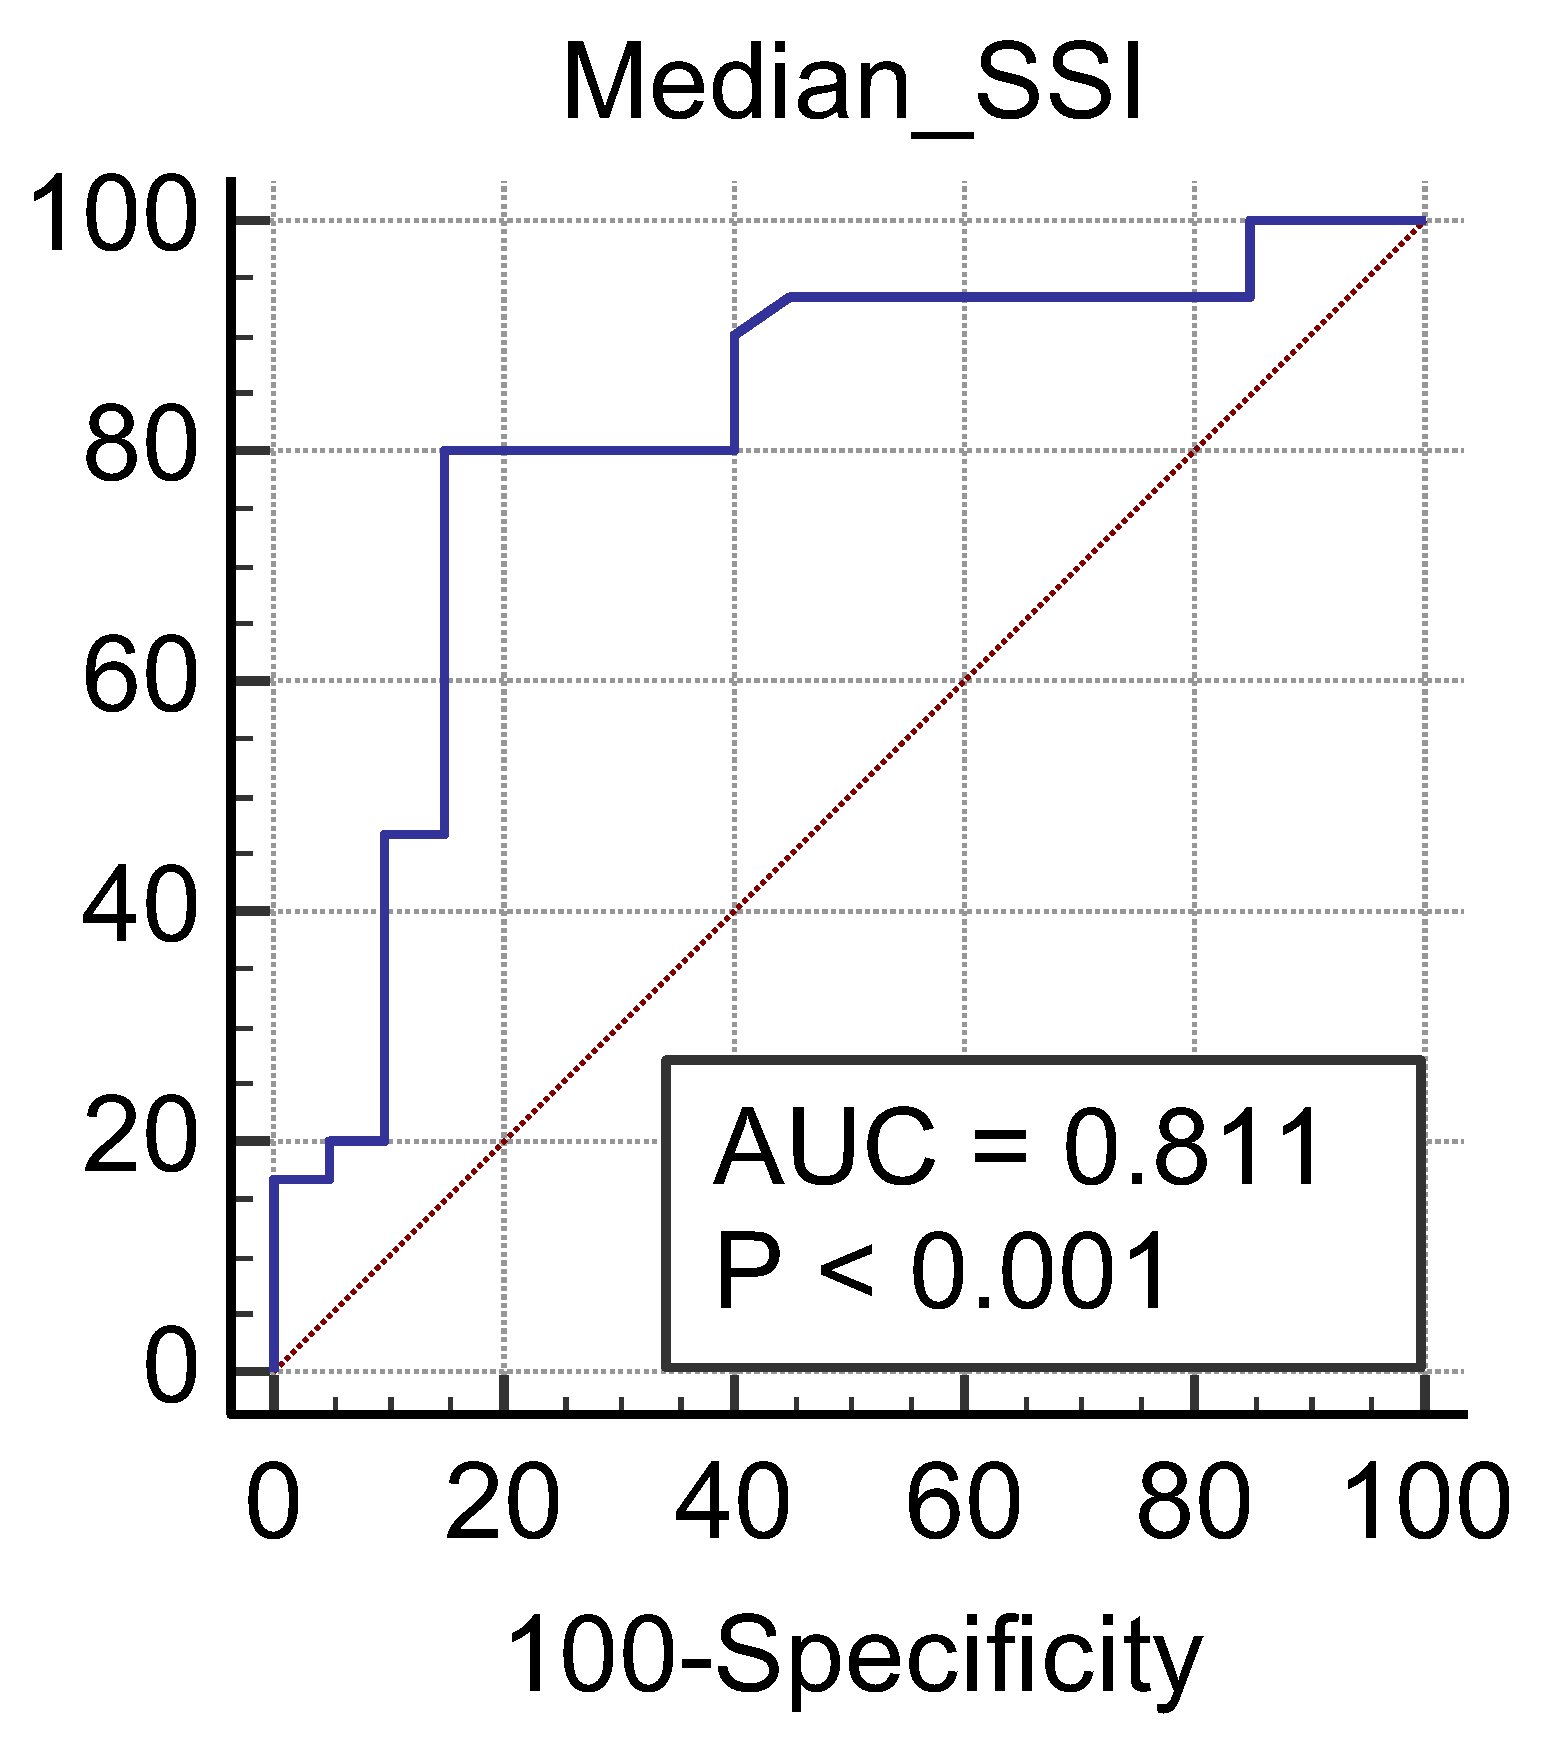

3. Results